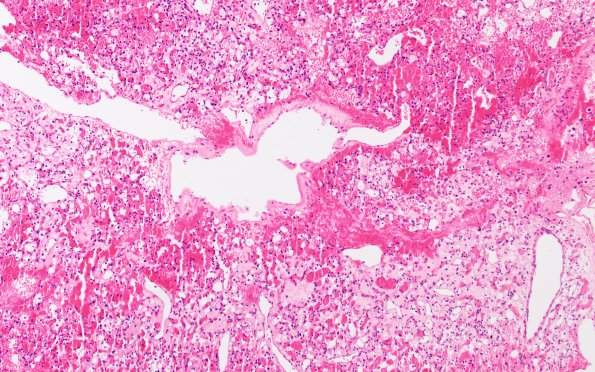

Washington University Experience | NEOPLASMS (MESENCHYMAL, NON-MENINGOTHELIAL) | Hemangioblastoma | 2B1 Hemangioblastoma (Case 2) H&E 2

2B1,2 H&E illustrates a highly vascular neoplasm composed of numerous thin walled vessels and intervening clear cells featuring generally monomorphic round to oval nuclei, with occasional hyperchromasia and pleomorphism. Many of the clear cells have a multivacuolated appearance. (H&E)